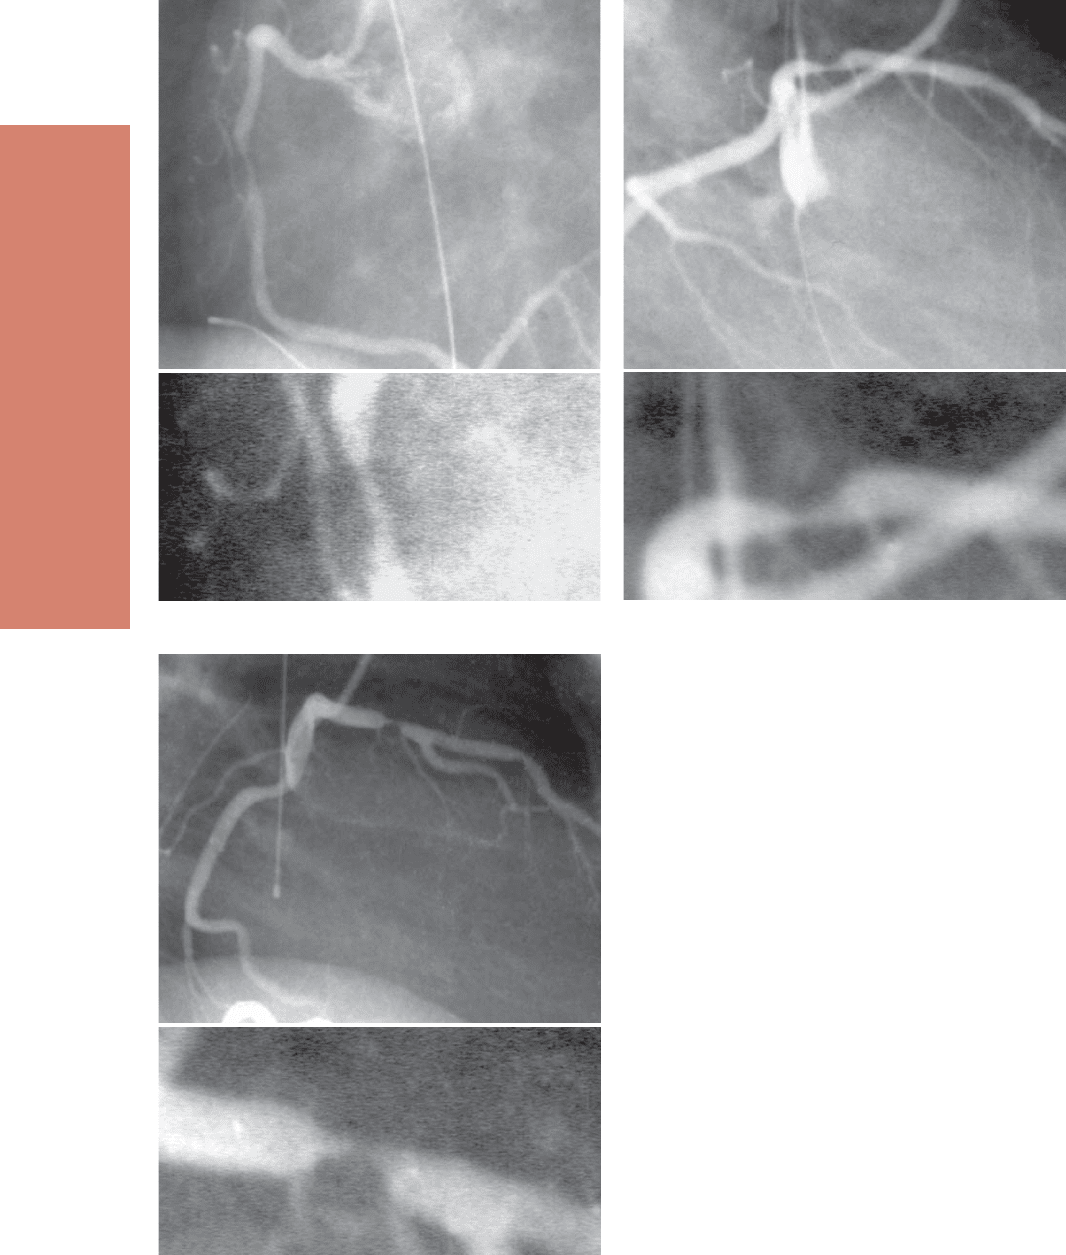

Устье и проксимальный отдел правой коро-

нарной артерии лучше всего видны в левой пе-

редней косой проекции 45–60°. Средний отдел

правой коронарной артерии хорошо визуализи-

руется как в правой передней косой проекции,

так и левой. Иногда используют латеральную

проекцию для визуализации средней трети пра-

вой коронарной артерии, которая в области crux

и задней межжелудочковой борозды определяет-

ся в левой передней косой проекции 30° с крани-

альной (20–30°) ангуляцией или в правой перед-

ней косой проекции 30° с небольшой (15–20°)

краниальной ангуляцией.